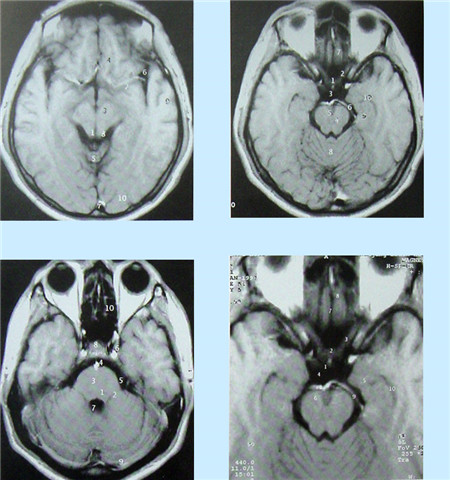

核磁共振血管成像(MRI)簡(jiǎn)介

核磁共振(MRI)又叫核磁共振成像技術(shù)。是繼CT后醫(yī)學(xué)影像學(xué)的又一重大進(jìn)步。自80年代應(yīng)用以來,它以極快的速度得到發(fā)展。其基本原理是:將人體置于特殊的磁場(chǎng)中,用無線電射頻脈沖激發(fā)人體內(nèi)氫原子核,引起氫原子核共振,并吸收能量。在停止射頻脈沖后,氫原子核按特定頻率發(fā)出射電信號(hào),并將吸收的能量釋放出來,被體外的接受器收錄,經(jīng)電子計(jì)算機(jī)處理獲得圖像,這就叫做核磁共振成像。

核磁共振成像無電離,對(duì)機(jī)體沒有不良影響。MRI對(duì)檢測(cè)腦內(nèi)血腫、腦外血腫、腦腫瘤、顱內(nèi)動(dòng)脈瘤、動(dòng)靜脈血管畸形、腦缺血、椎管內(nèi)腫瘤、脊髓空洞癥和脊髓積水等顱腦常見疾病很有效。

核磁共振成像設(shè)備價(jià)格昂貴,檢查費(fèi)用也較高,它與CT都可以提供斷層的靜態(tài)掃描圖像。

數(shù)字減影血管造影DSA腦血管圖像顯示 核磁共振MRI掃描腦組織圖像